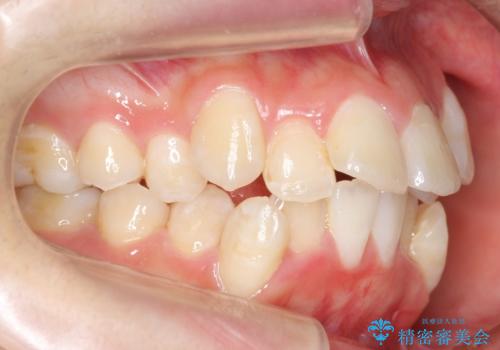

八重歯の治療 仕上がり重視で

- 八重歯を主訴に来院。

仕上がり重視とのことで、小臼歯を抜歯し、スタンダードな治療方法で仕上げています。

上下の小臼歯を抜歯しています。

矯正用インプラントアンカーを使用してしっかり前歯を下げたため、口元が大きく改善しています。